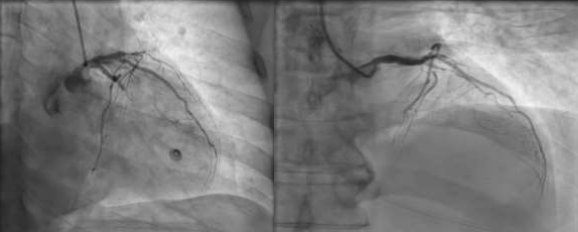

72 Year old male with no comorbidities, was brought to ER in a state of unresponsiveness since 1 hour. Initial evaluation revealed normal vitals signs, GCS: E1V1M1, GRBS of 180mg/dL. ABG was also normal. He was intubated for airway protection. ECG changes (FIG1) were present as shown in the figure. ECHO done showed apical hypokinesia with LVEF 20%. He underwent a CT brain which revealed no acute infarct/ bleed. Troponin was elevated. He was taken up for primary PCI which revealed LAD and LCx having 100% thrombotic occlusions (FIG 2) which were successfully treated by 1X DES in LAD and 1xDES in LCx achieving TIMI 3 flow (FIG3) . Patient was extubated the following day as he regained consciousness with no end organ damage or shock. Timely intervention and inclusion of two arteries as culprit vessels, with such peculiar presentation as well as the ECG changes makes it a case of rarity. It also signifies the importance of treating the condition on an emergent basis to aid in complete recovery.

FIG 3: POST PCI